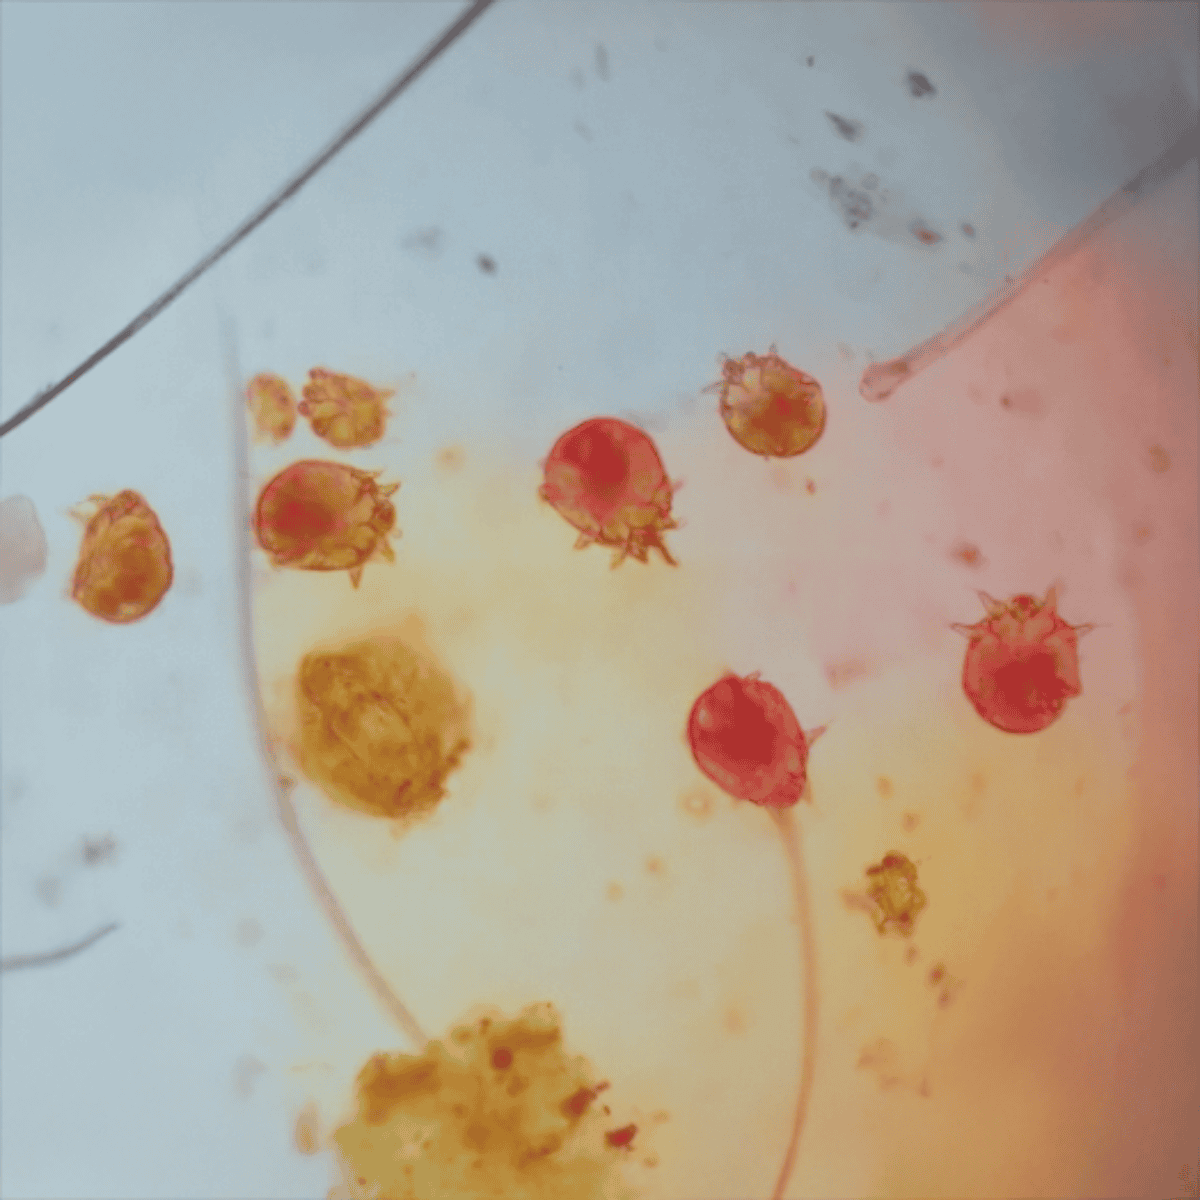

Skin scrapings are a common procedure used to identify mange. During this process, a small sample of the dog’s skin is gently scraped. The sample is then examined under a microscope to detect mites.

Tests such as skin scrapings are minimally invasive and typically cause little to no discomfort. They are an accurate way to confirm mange by identifying the organism present in the skin and allow for a precise diagnosis, guiding effective treatment.